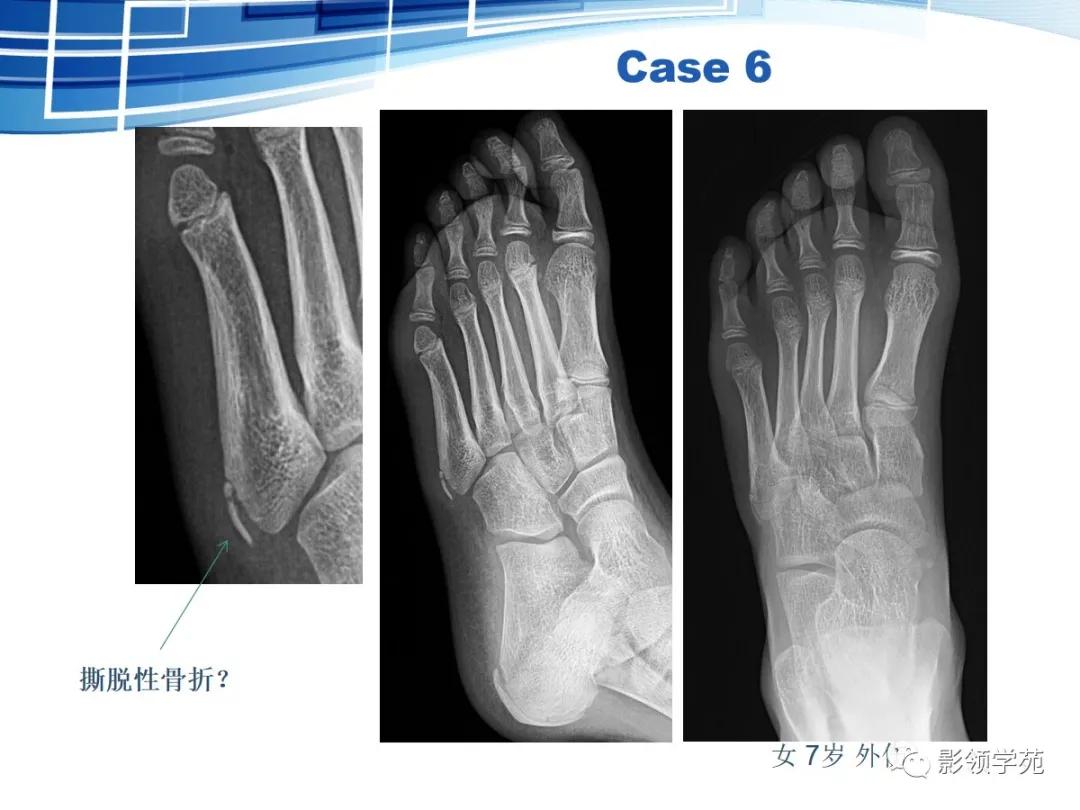

第五跖骨基底部骨折,常为横行骨折,即骨折线垂直于跖骨骨干,它是由于腓侧短肌肌腱应力所引起的撕脱骨折,也称“JONES骨折”。该骨折应与第五跖骨粗隆突起鉴别,尤其是9-15岁的儿童,常常可以出现第五跖骨基底部的骨骺,常表现为纵行透亮线,骨片边缘一般规则光滑,周围软组织无明显肿胀。

第五跖骨粗隆存在独立的骨化中心,并且可有一个或多个骨化中心,常见于10~15岁儿童。一般25岁左右与第五跖骨其余部分融合。

我们所常见的第五跖骨基底部骨折的骨折线一般都是垂直于长轴的,平行于第五跖骨长轴的骨折非常罕见。从外力方向、方式来发现,很难使第五跖骨基底部发生纵形骨折,而该处确实存在骨骺,大量的误诊就是把骨骺当骨折。